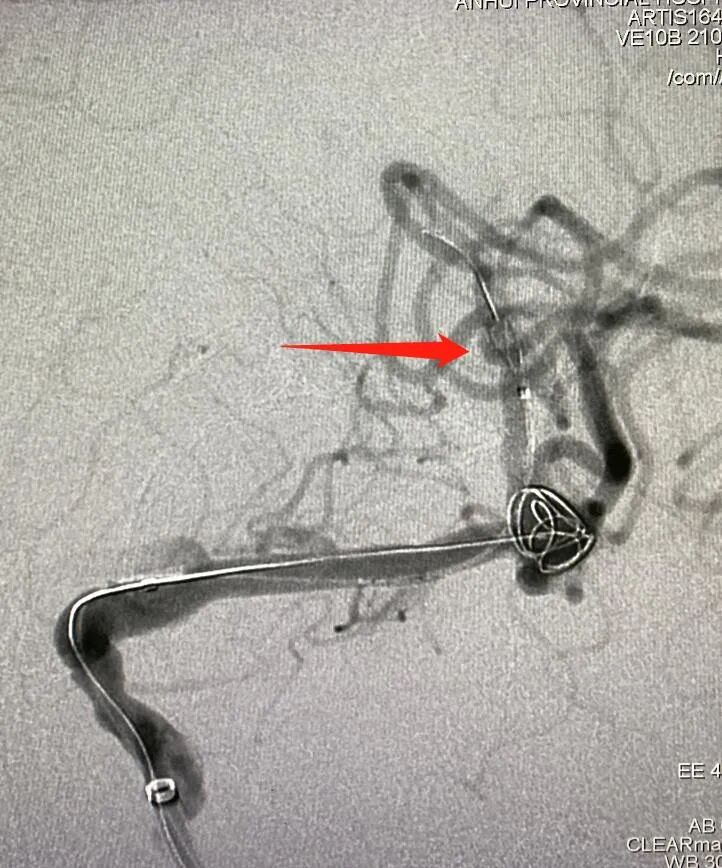

工作位角度

什么达医畅疗·第一期 | 畅医达(Choydar)17小系统血流导向装置治疗大脑中动脉动脉瘤两例_https://www.jmylbn.com_新闻资讯_第24张

术后正侧位造影片提示颅内血管显影良好,支架打开充分,瘤颈处推密,贴壁良好,动脉瘤内造影剂滞留明显。